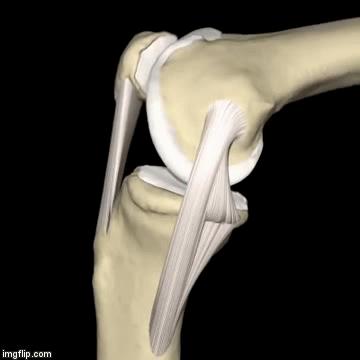

主要是长在骨头上的肌肉和韧带。在膝盖的四周都有不同的肌肉、韧带,从不同的角度发力来维持膝关节和膝盖骨的稳定;倘若哪一侧太弱,其他侧太强,就会打破原有的稳定状态,出现不同的腿型、不同方向的膝盖骨移位。

2.其次,再来看一看,当您屈、伸腿时,膝关节具体是怎么移动的?

正常情况下 ,如动图所示,在您屈膝(弯腿)的时候,膝盖骨(俗称菠萝盖)会往内下方移动;而伸膝(伸腿)的时候,膝盖骨会往外上方移动。

正常情况,每一个人的膝关节骨头表面之间都有一层纤维软骨,起着润滑关节,帮助您在屈伸腿时更灵活;同时支撑您自身重力和缓冲减震的作用。一旦磨损退变后,逐渐出现疼痛等症状。